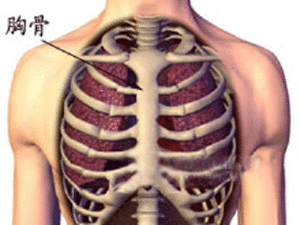

胸骨骨折臨床表現

胸骨處腫脹、壓痛,可伴有呼吸道、胸腔血管或脊柱損傷。